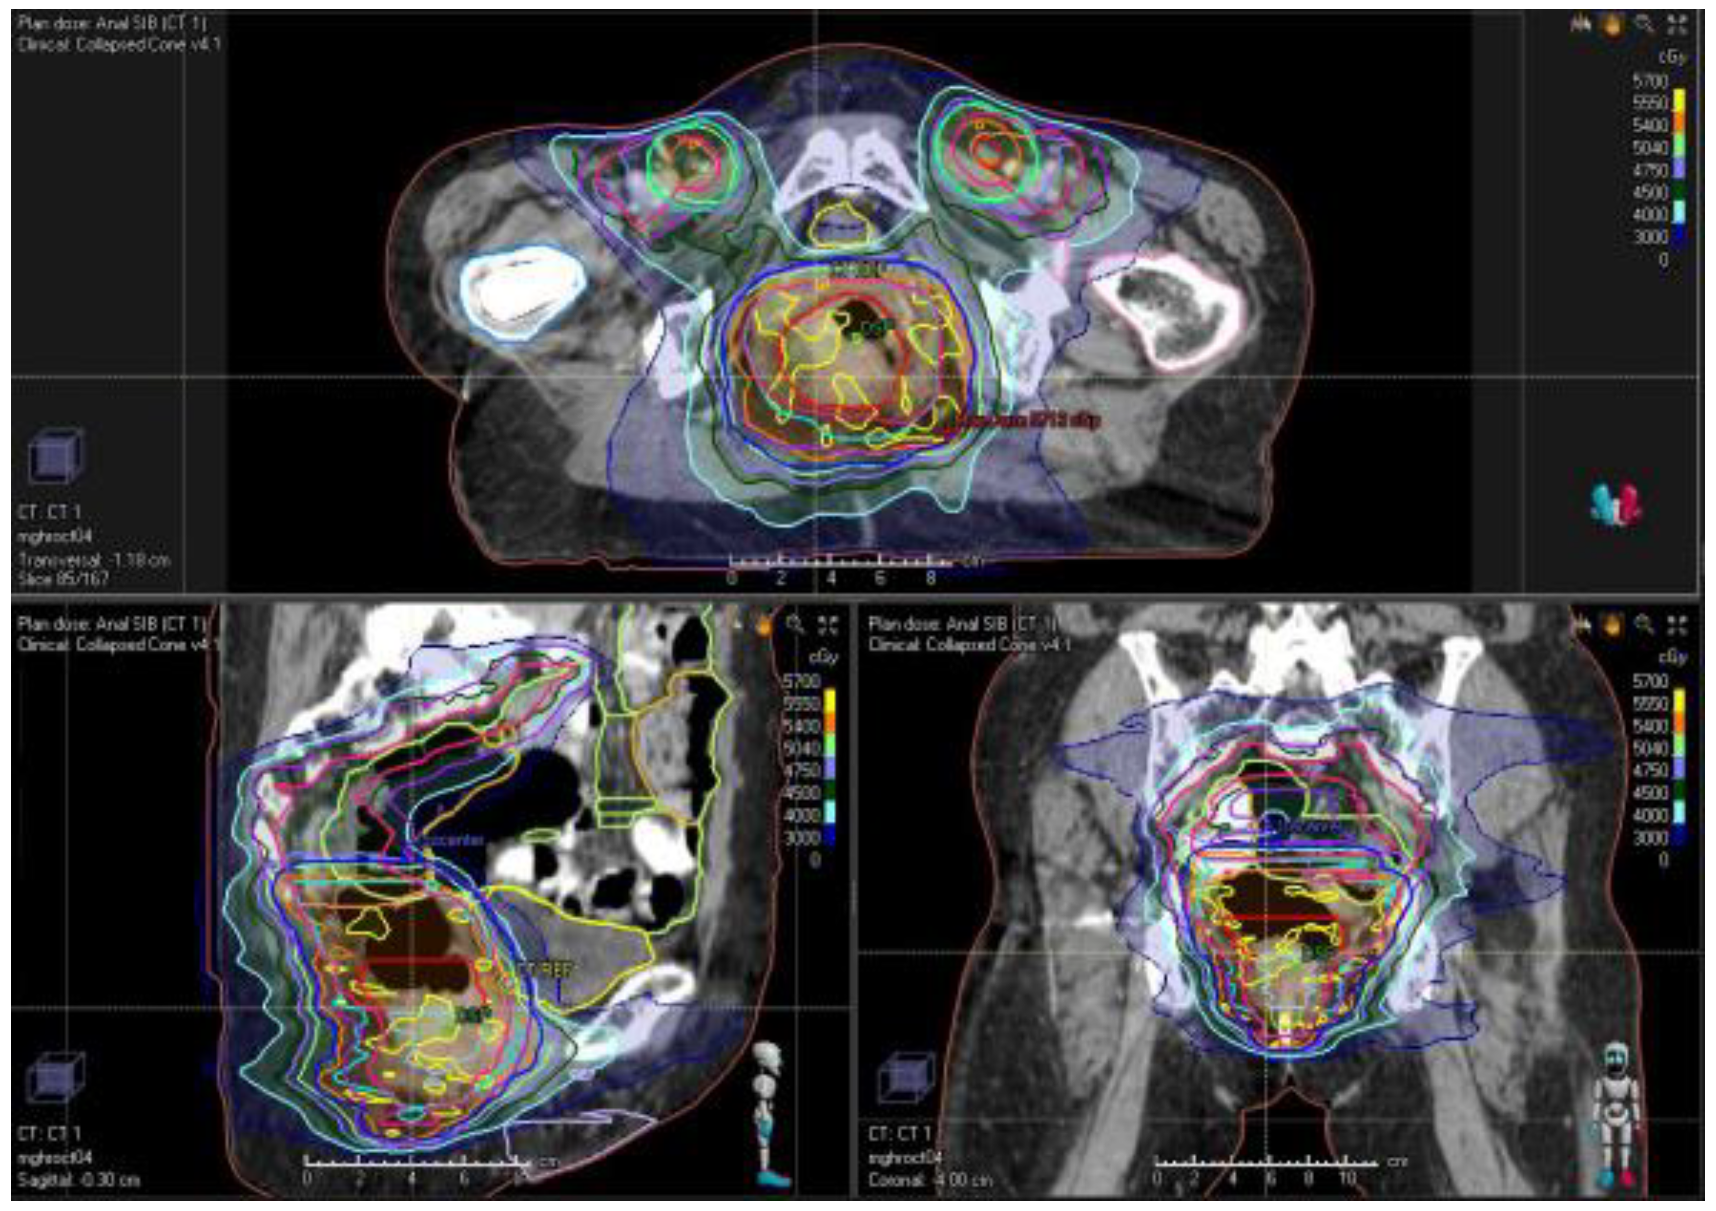

8. Intensity-Modulated Radiation Therapy: RTOG 05-29

10. Treatment Planning and Delivery: Institutional Practice and Recent Advances

12. Timing of Treatment Evaluation and Persistent/Recurrent Disease